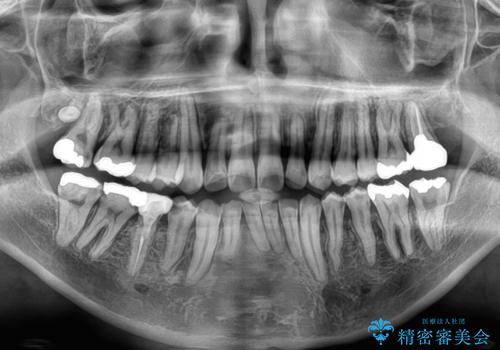

- 主張してる上の前歯を気にして来院された患者様です。

上の前歯が出ているものの、口元が出っ歯というわけではなかったため、非抜歯矯正にて治療を行うこととしました。

下顎に対して上顎歯列が全体的に前方に位置しており、特に右側の奥歯の咬み合わせの前後のズレが大きいため、補助装置を用いて咬み合わせを改善することとしました。